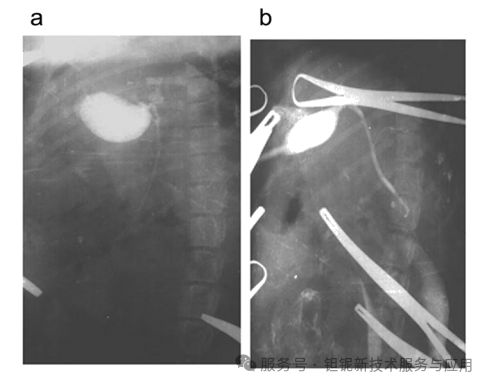

犬胆道造影中,30% 稀土TaO₄可清晰显示直径≥7 mm 的结石,肝内胆管分支显影分辨率达 0.5 mm(图 9)。相比之下,泛影葡胺组黏膜出现大面积坏死,而 稀土TaO₄组仅见轻度淋巴细胞浸润(图 10、图 11)。

图9.使用10% (a,b)、20% (c,d)和30 % (e,f)placeLOT凝胶混悬液对犬进行术中胆囊胆管造影。相同图像放大4倍(b,d,f)。